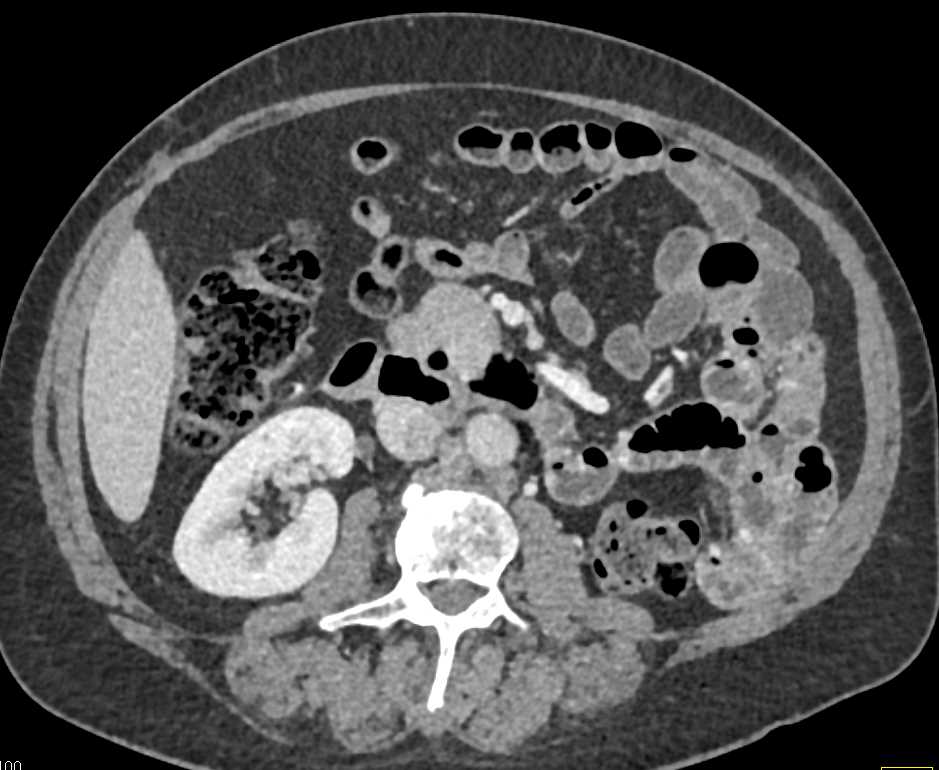

Paraganglioma